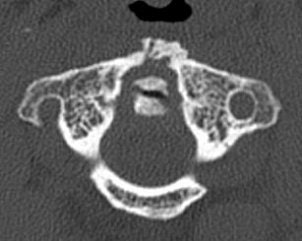

The 0.5-mm slices offer fine bone detail, but pay a price on the soft-tissue images in terms of soft-tissue differentiation. Whereas the thicker (5-mm) slices fail to show the bone detail of the fracture well, but possess greater contrast resolution on the soft-tissue window to differentiate spinal cord from surrounding spinal fluid.

![]() ![]() |

One caveat for cervical CT pertained to clearing the C-spine. If ruling out instability is the goal, it is important to start with a static radiological evaluation to look for fractures, Cinnamon said. Dynamic radiological evaluations, such as a flexion-extension exam or dynamic MRI, may also be necessary because CT alone cannot evaluate for instability.